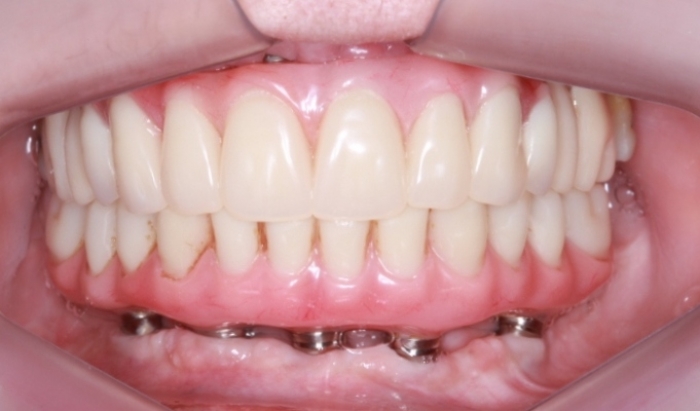

Próteses fixas definitivas em resina em Outubro de 2016 - Clínica Cliniface

Próteses fixas definitivas em resina em Outubro de 2016